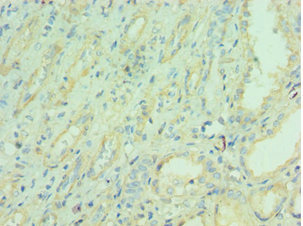

Immunohistochemistry of paraffin-embedded human liver tissue using CSB-PA015422ESR2HU at dilution of 1:100

Immunohistochemistry of paraffin-embedded human kidney tissue using CSB-PA015422ESR2HU at dilution of 1:100